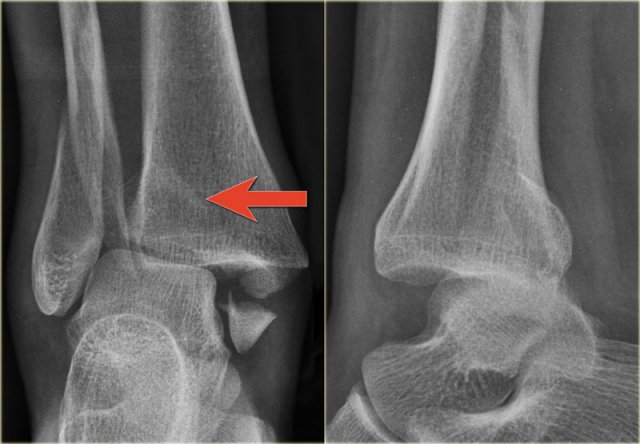

Example 2

• First impression

There is a fracture of the posterior malleolus.

Classification according to Weber is not possible.

An isolated fracture of the posterior malleolus is uncommon, but as part of a supination exorotation (Weber B) or pronation exorotation injury (Weber C) it is quite common.

So we have to re-examine the films to look for signs of a Weber B or C fracture.

• Re-examination

No sign of an oblique fracture of the lateral malleolus, so we can exclude a Weber B fracture.

There is still the possibility of a Weber C fracture, i.e. medial rupture or avulsion, high fibular fracture and finally a posterior malleolar fracture.

Now we notice the subtle avulsion of the medial malleolus (red arrow).

Additional radiographs of the lower extremity demonstrate a high fibular fracture (blue arrow).

• Final report

Weber C stage 4.